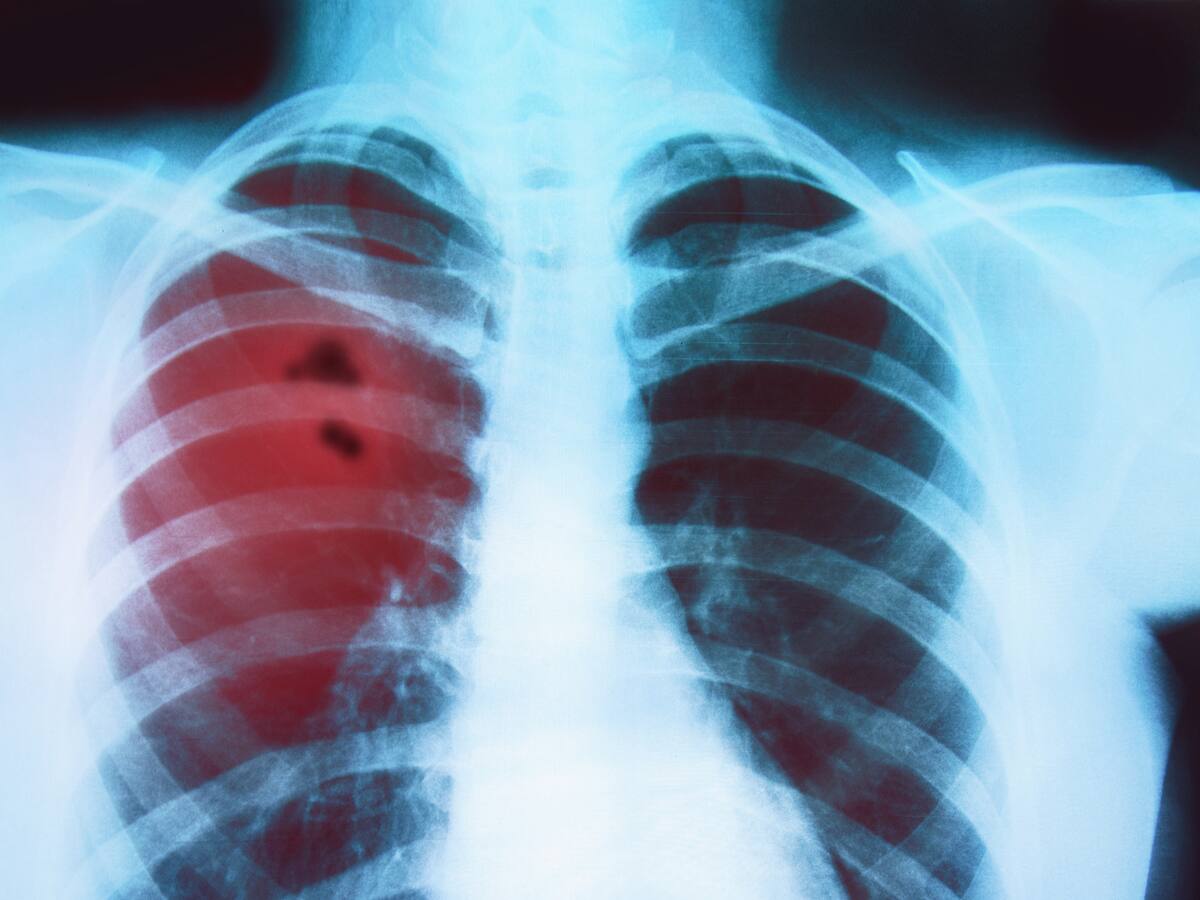

Niña de siete años fue diagnosticada con cáncer de mama

Este inédito caso, ocurrido en Chile, tiene desconcertados a los expertos, quienes evalúan los posibles pasos a seguir.

Este inédito caso, ocurrido en Chile, tiene desconcertados a los expertos, quienes evalúan los posibles pasos a seguir.